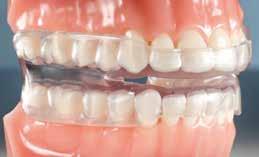

A kivehető helyben-tartók legfontosabb eleme a mindkét fogívet összekötő ún. Splint (19. kép), amely egyrészt saggitálisan tartja a helyén a mandibulát, hogy ne csússzon vissza hátrafelé, másrészt segít a harapás zártan tartásában a növekedés teljes befejeződéséig.